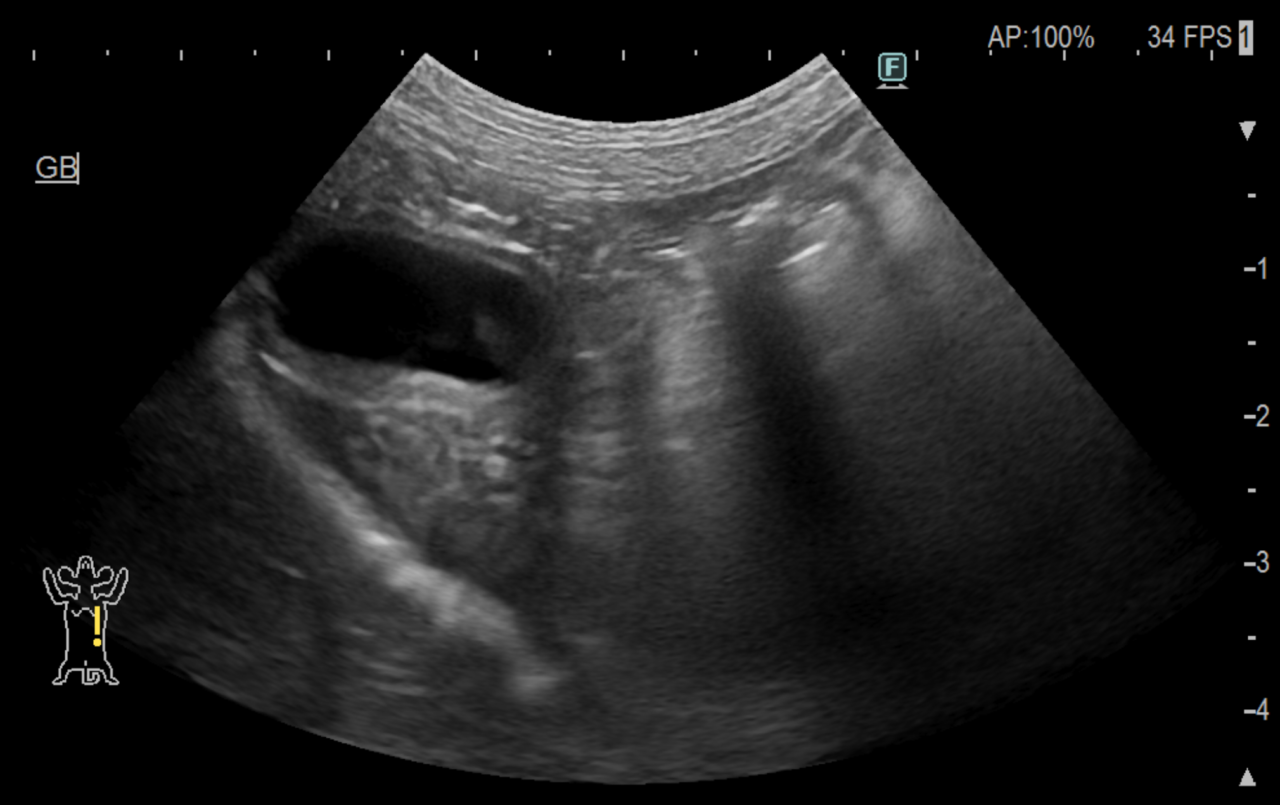

若齢の小型犬が朝から嘔吐下痢がありぐったりしているとのことでかかりつけ医を受診しました。そこでは腹水が確認され、検査をしてみると腹腔内出血をしているようだったとのことで急遽、当センターへ紹介がありました。

検査を行い、胆嚢や膵臓が浮腫状態であること、肝数値が上昇していることなどからアナフィラキシー症状であると診断し、アレルギーに対する治療を行なっています。

近年、アナフィラキシーにより腹腔内出血を起こす症例報告がありましたがメカニズムはわかっていません。肝臓などの臓器から出血が起こるとされていますが、多くは重篤にならずに内科治療で改善します。